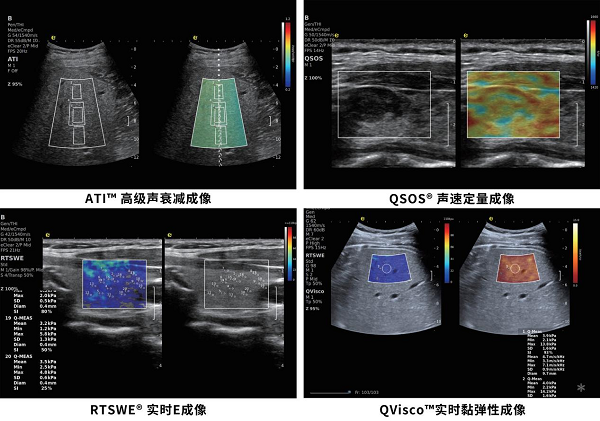

雅克·苏凯院士,这位曾发明全球第一台全数字化彩超、将E超技术引入临床的科学巨匠,十余年前便将弹性E成像理念带到中国。如今,他亲率研发团队,在中国完成了这项技术的全面进化。此次亮相ECR 2026的逸超“E型”定量超声,搭载OmniSound®平面波超快速平台,采集帧频高达25000帧/秒,是传统彩超的200余倍。正是这一极速平台,让第二代2D实时剪切波弹性成像RTSWE®、QSOS®声速定量成像、ATI®高级声衰减成像等尖端技术得以实现并临床落地,使组织硬度、声速、衰减系数成为可重复的“超声生物标记物”。